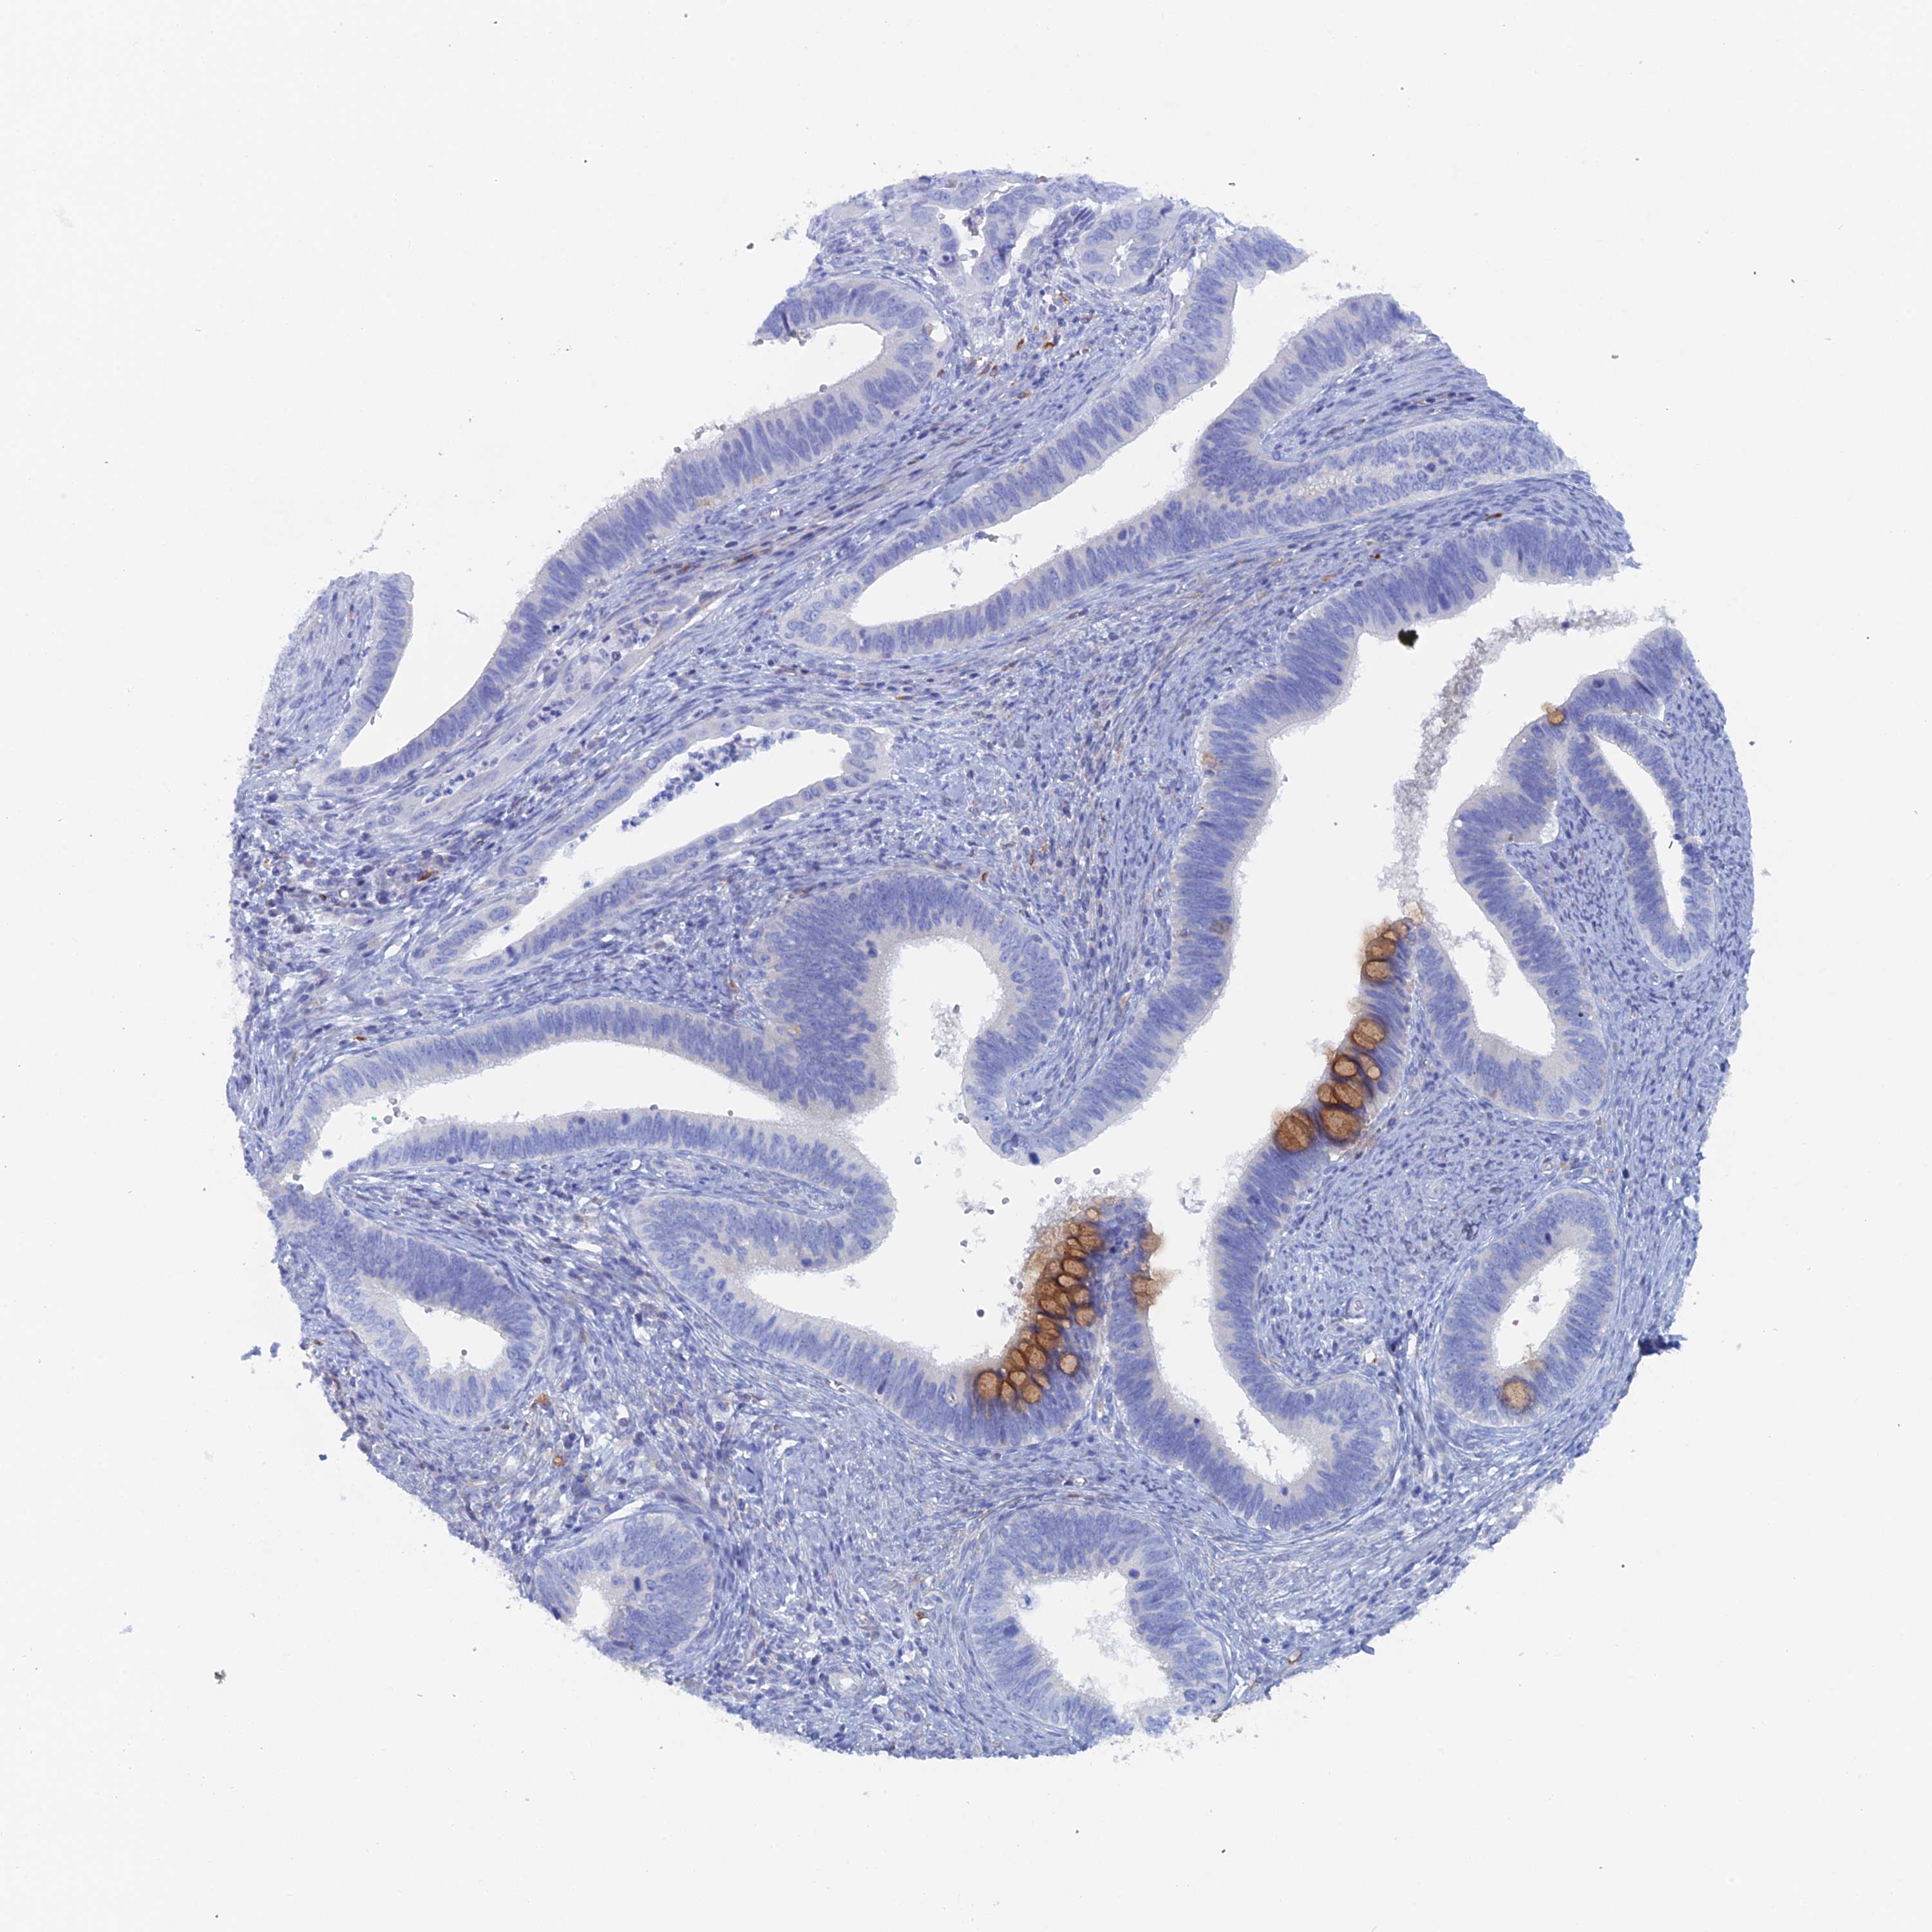

CERVICAL CANCER - Protein expressioni

A mouse-over function shows sample information and annotation data. Click on an image to view it in a full screen mode. Samples can be filtered based on level of antibody staining by selecting one or several of the following categories: high, medium, low and not detected. The assay and annotation is described here.

Note that samples used for immunohistochemistry by the Human Protein Atlas do not correspond to samples in the TCGA dataset.

Antibody stainingi

Antibody staining in the annotated cell types in the current human tissue is reported as not detected, low, medium, or high, based on conventional immunohistochemistry profiling in selected tissues. This score is based on the combination of the staining intensity and fraction of stained cells.

Each image is clickable and will lead to virtual microscopy that enables deeper exploration of all samples and also displays staining intensity scores, fraction scores and subcellular localization as well as patient and tissue information for each sample.

Antibody HPA040758

Staining

High

Medium

Low

Not detected

Intensity

Strong

Moderate

Weak

Negative

Quantity

>75%

75%-25%

<25%

None

Location

Nuclear

Cytoplasmic/membranous

Cytoplasmic/membranous,nuclear

Squamous cell carcinoma, NOS

Adenocarcinoma, NOS